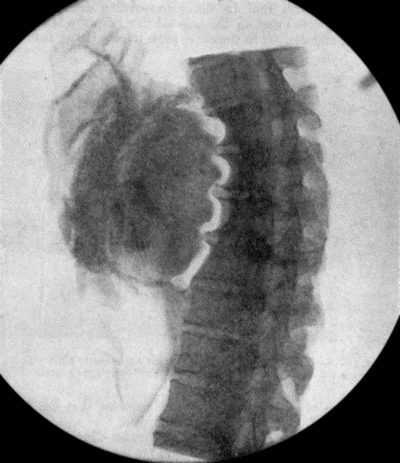

71.Radiogram of Aneurysm of Aorta 303

73.Radiogram of Innominate Aneurysm after Treatment by Moore-Corradi method 309